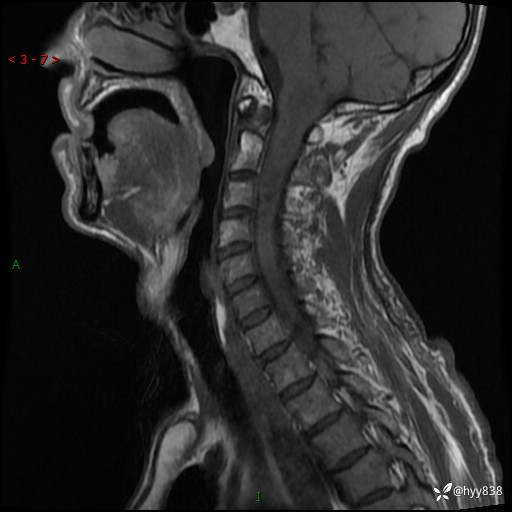

晨读典型病例分享。老年男性,右手麻木3年,四肢无力4月---结果公布~

主诉:右手麻木3年,四肢无力4月

简要病史:患者约于2年前无明显诱因出现右手麻木伴有精细活动差,无行走不稳,家属将患者送至当地县人民医院行颈椎MR提示:颈髓占位性病变。患者未系统治疗治疗。后病情逐渐加重,4个月前出现四肢无力,右侧为甚,行走不稳,伴有四肢感觉减退,伴有大便偶有失禁,现患者及家属为求进一步治疗入我院,遂以“椎管占位”收住我科。 发病以来,患者精神饮食睡眠好,大小便正常,体力体重未见明显改变。

辅助检查:MRI

临床诊断:椎管占位

颈椎MRI平扫(sag T1WI+T2WI-fs+axi T2WI)